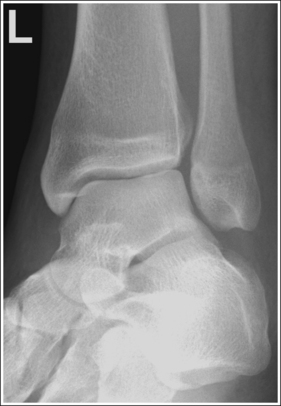

See Figure 6-46 and Box 6-10.

The ankle is demonstrated in an AP projection. The medial mortise (tibiotalar articulation) is open, and the distal tibia and talus are superimposed over the distal fibula by a small amount (0.125 inch [3 mm]), closing the lateral mortise (fibulotalar articulation).

• An AP projection of the ankle is obtained by positioning the patient supine on the image table, with the leg fully extended and the foot dorsiflexed until its long axis is placed in a vertical position (Figure 6-47). In this position, the intermalleolar line (imaginary line drawn between the medial and lateral malleoli) is at a 15- to 20-degree angle with the IR. The medial malleolus is positioned farther from the IR than the lateral malleolus.

• Evaluating the openness of the tibiotalar joint. On an AP ankle projection, determine whether an open joint was obtained and whether the tibia is demonstrated without foreshortening by evaluating the anterior and posterior margins of the distal tibia. On an AP ankle projection with accurate positioning, the anterior margin is demonstrated approximately 0.125 inch (3 mm) proximally to the posterior margin (see Figure 6-48). If the proximal lower leg was elevated or the central ray was centered proximal to the tibiotalar joint, the anterior tibial margin is projected distally, resulting in a narrowed or obscured tibiotalar joint space (see Image 34). If the distal lower leg was elevated or the central ray was centered distal to the tibiotalar joint, the anterior tibial margin is projected more proximally to the posterior margin than on an AP ankle projection, expanding the tibiotalar joint space and demonstrating the tibial articulating surface (see Image 35).

The tibiotalar joint space is at the center of the exposure field. The distal fourth of the tibia and fibula, the talus, and the surrounding ankle soft tissue are included within the collimated field.

• To place the tibiotalar joint in the center of the image, center a perpendicular central ray to the ankle midway between the malleoli. The medial malleolus is located at the same level as the tibiotalar joint space. Open the longitudinal collimation to include the calcaneus and one fourth of the distal lower leg. Transverse collimation should be to within 0.5 inch (1.25 cm) of the ankle skin line.